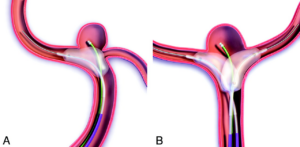

Dodatkowe wyzwanie stanowiły tętniaki wewnątrzczaszkowe o szerokiej szyi (szeroka szyja w uproszczeniu oznacza szerokie połączenie tętniaka z tętnicą macierzystą) oraz tętniaki zlokalizowane w podziale tętnicy. Pierwotnie znajdowały się one praktycznie poza zasięgiem metod przeznaczyniowych, z uwagi na podwyższone ryzyko wystawania spiral z worka tętniaka do naczynia macierzystego. Przełomem okazały się techniki remodelingu balonowego (BRT) oraz embolizacji z użyciem stentu (SACT). Główną ich ideę stanowi dodatkowy element podpierający i stabilizujący spirale w obrębie worka tętniaka – odpowiednio balon (napełniany tylko czasowo w trakcie embolizacji i usuwany w finalnym etapie zabiegu) lub stent jako element wprowadzany na stałe.

Rysunek 1. Zastosowanie jednego (a) lub dwóch (b) cewników balonowych w embolizacji tętniaka. Uwaga: W celu osiągnięcia większej przejrzystości rysunku nie umieszczono na nim spiral w worku tętniaka.

Balon umieszczony na przebiegu szyi tętniaka odgrywa niebagatelną rolę w przypadku pęknięcia tętniaka podczas zabiegu. Bezzwłoczne wypełnienie balonu pozwala natychmiast zatrzymać krwawienie i uzyskać dodatkowy czas na embolizację tętniaka zabezpieczając pacjenta przed masywniejszym krwotokiem. Wykazano, iż w sytuacji śródzabiegowego krwawienia z tętniaka zastosowanie balonu wiąże się ze zdecydowanie wyższym prawdopodobieństwem niezmienionego lub lepszego niż wyjściowy stanu klinicznego chorego w porównaniu do techniki klasycznej.